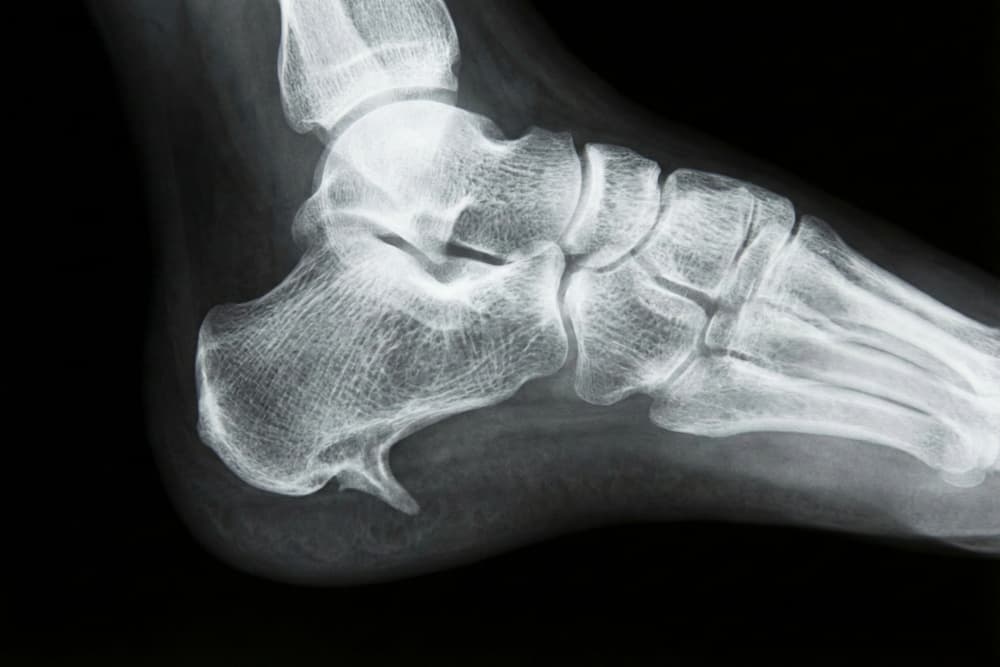

- Hælsporer: Knogleudvækster på hælbenet.

- Haglunds deformitet: En knoglefremspring bag på hælen.